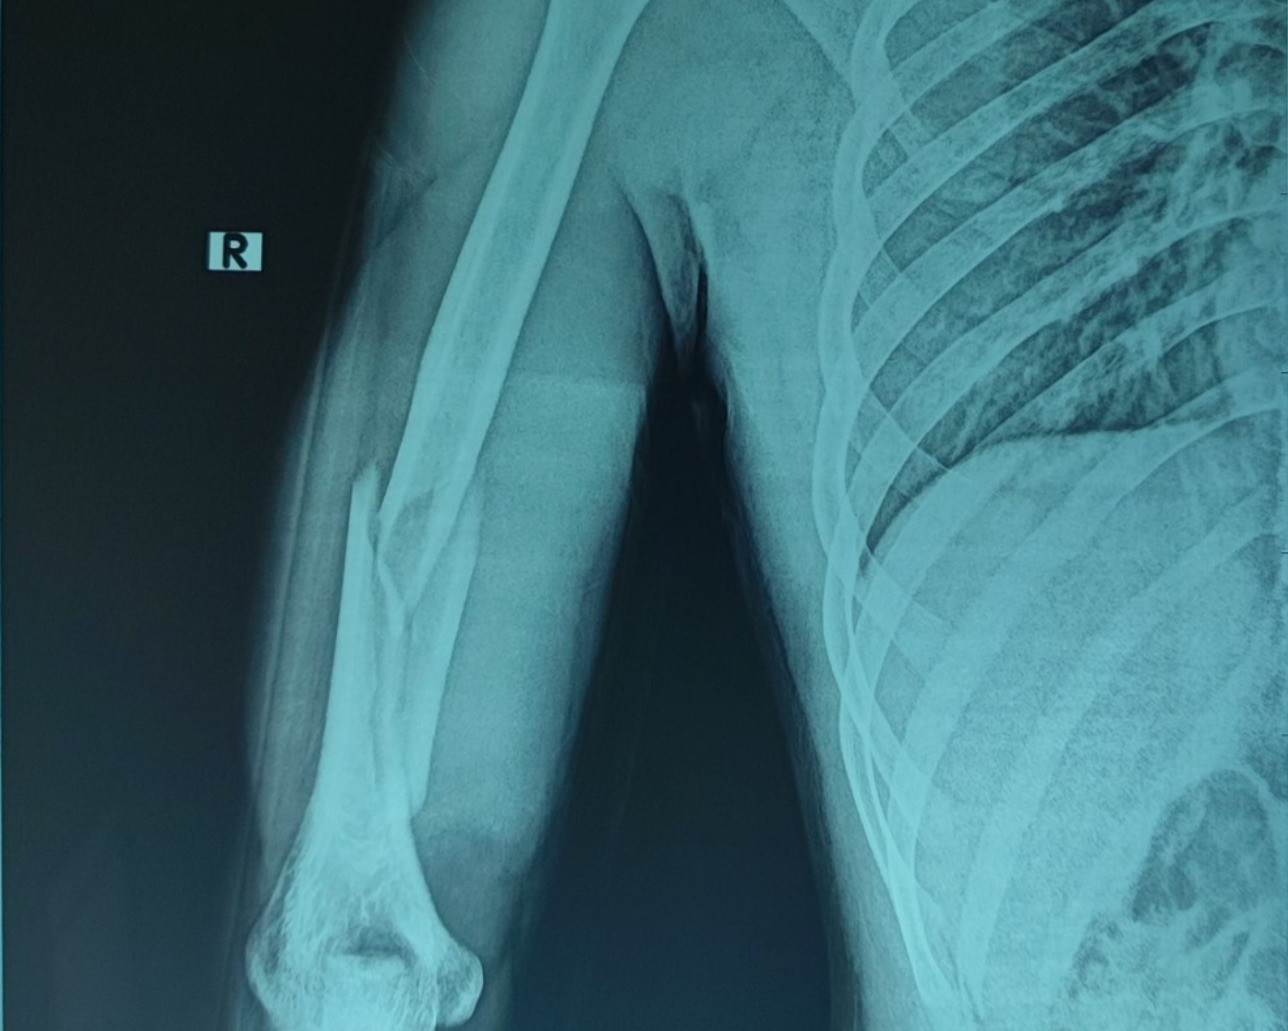

Thạc sĩ, bác sĩ Nguyễn Văn Phan, Khoa Phẫu thuật Chấn thương chung, Bệnh viện Hữu nghị Việt Đức, cho biết bệnh nhân là H.H.C. (21 tuổi), là sinh viên tại Hà Nội. Anh C. đến bệnh viện trong tình trạng sưng đau, biến dạng, hạn chế vận động cánh tay phải. Hình ảnh X-quang cho thấy xương cánh tay phải bị gãy chéo vát ở 1/3 dưới, có mảnh rời cánh bướm lớn.

Hình ảnh X-quang cho thấy xương cánh tay phải bị gãy chéo vát ở 1/3 dưới, có mảnh rời cánh bướm lớn. Ảnh: BVCC

Hình ảnh chụp X-quang kiểm tra sau mổ cho thấy giải phẫu xương cánh tay được phục hồi. Sau 4 ngày điều trị, người bệnh được ra viện. Tái khám sau 1 tháng, vết mổ liền sẹo tốt, vận động cánh cẳng tay phải được, không tê bì yếu liệt đầu chi.